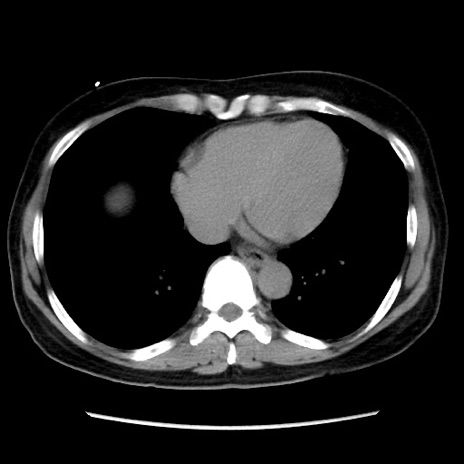

症例10(横断像)

【症例】 50歳代女性

【主訴】 腹痛

【現病歴】前日生レバーを食べた。今朝に排便あり。 昼前に突然発症の腹痛を生じ、当院救急外来を受診した。

【既往歴】 子宮筋腫にてで子宮全摘後

【身体所見】 意識清明、腹部:平坦、軟、下腹部やや左を中心に圧痛・反跳痛あり、筋性防御あり

【データ】WBC 7800、CRP 0.07